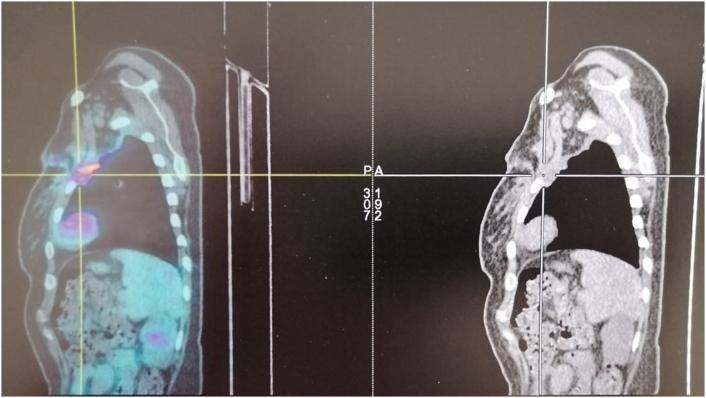

This is a 45-year-old woman who underwent monobloc resection of a mass carrying the anterior arch of the second left rib associated with a wedge resection of a nodule at the left upper lobe. Histology confirmed that it was a malignant melanoma. Her history was negative for melanocytic lesions, physical examination and imaging had failed to identify a primary lesion. The patient is currently under nivolumab for Stage IV melanoma and does not present any complications or recurrence during the long term follow up.

这是一名45岁女性,她接受了携带左第二肋前弓肿物的整块切除,并联合左上叶结节的楔形切除。组织学证实为恶性黑色素瘤。她的黑素细胞病变病史为阴性,体格检查和影像学检查均未发现原发灶。该患者目前正在接受纳武单抗治疗IV期黑色素瘤,在长期随访中未出现任何并发症或复发。